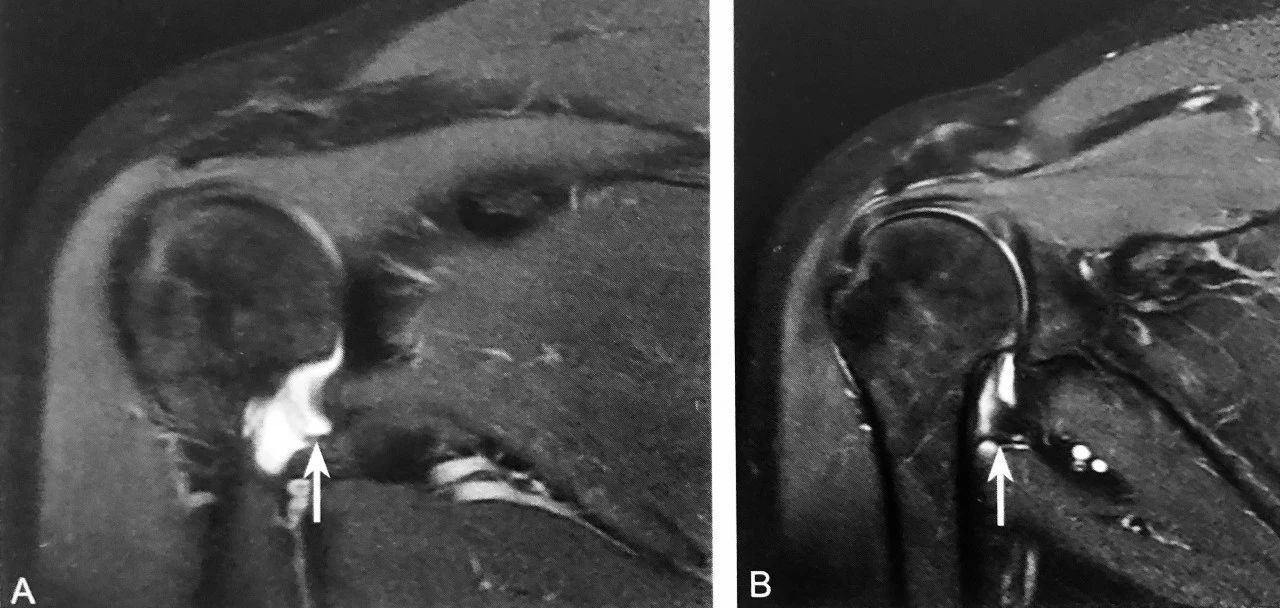

双 曲 奇 饼 征

A、B 图为同一患者,抑脂 T2WI 示上盂唇周围两条线样高信号,其中一条高信号代表上盂唇的撕裂,另外一条指的是盂唇上隐窝,形成双曲奇饼征,提示上盂唇由前向后撕裂,即 SLAP 损伤(箭头所示)

判读要点:

1、SLAP 损伤的特征性表现;

2、在肩关节常规 MRI 斜冠状位 T2WI 或 MRI 关节造影图像显示,上盂唇内出现两条高信号;

3、具有较高的特异性,但敏感性较低。

J 征

A、B 图为同一患者, 压脂 T2WI 示右肩关节腋囊少许积液,右盂肱下韧带肱骨附着处部分撕裂并回缩,形成 J 征

1、肱骨附着处撕脱的直接征象;

2、在肩关节 MRI 斜冠状位压脂 T2WI 或 MRI 造影上观察;

3、右肩 HAGL 损伤表现为 J 征,左肩 HAGL 损伤表现为反 J 征。